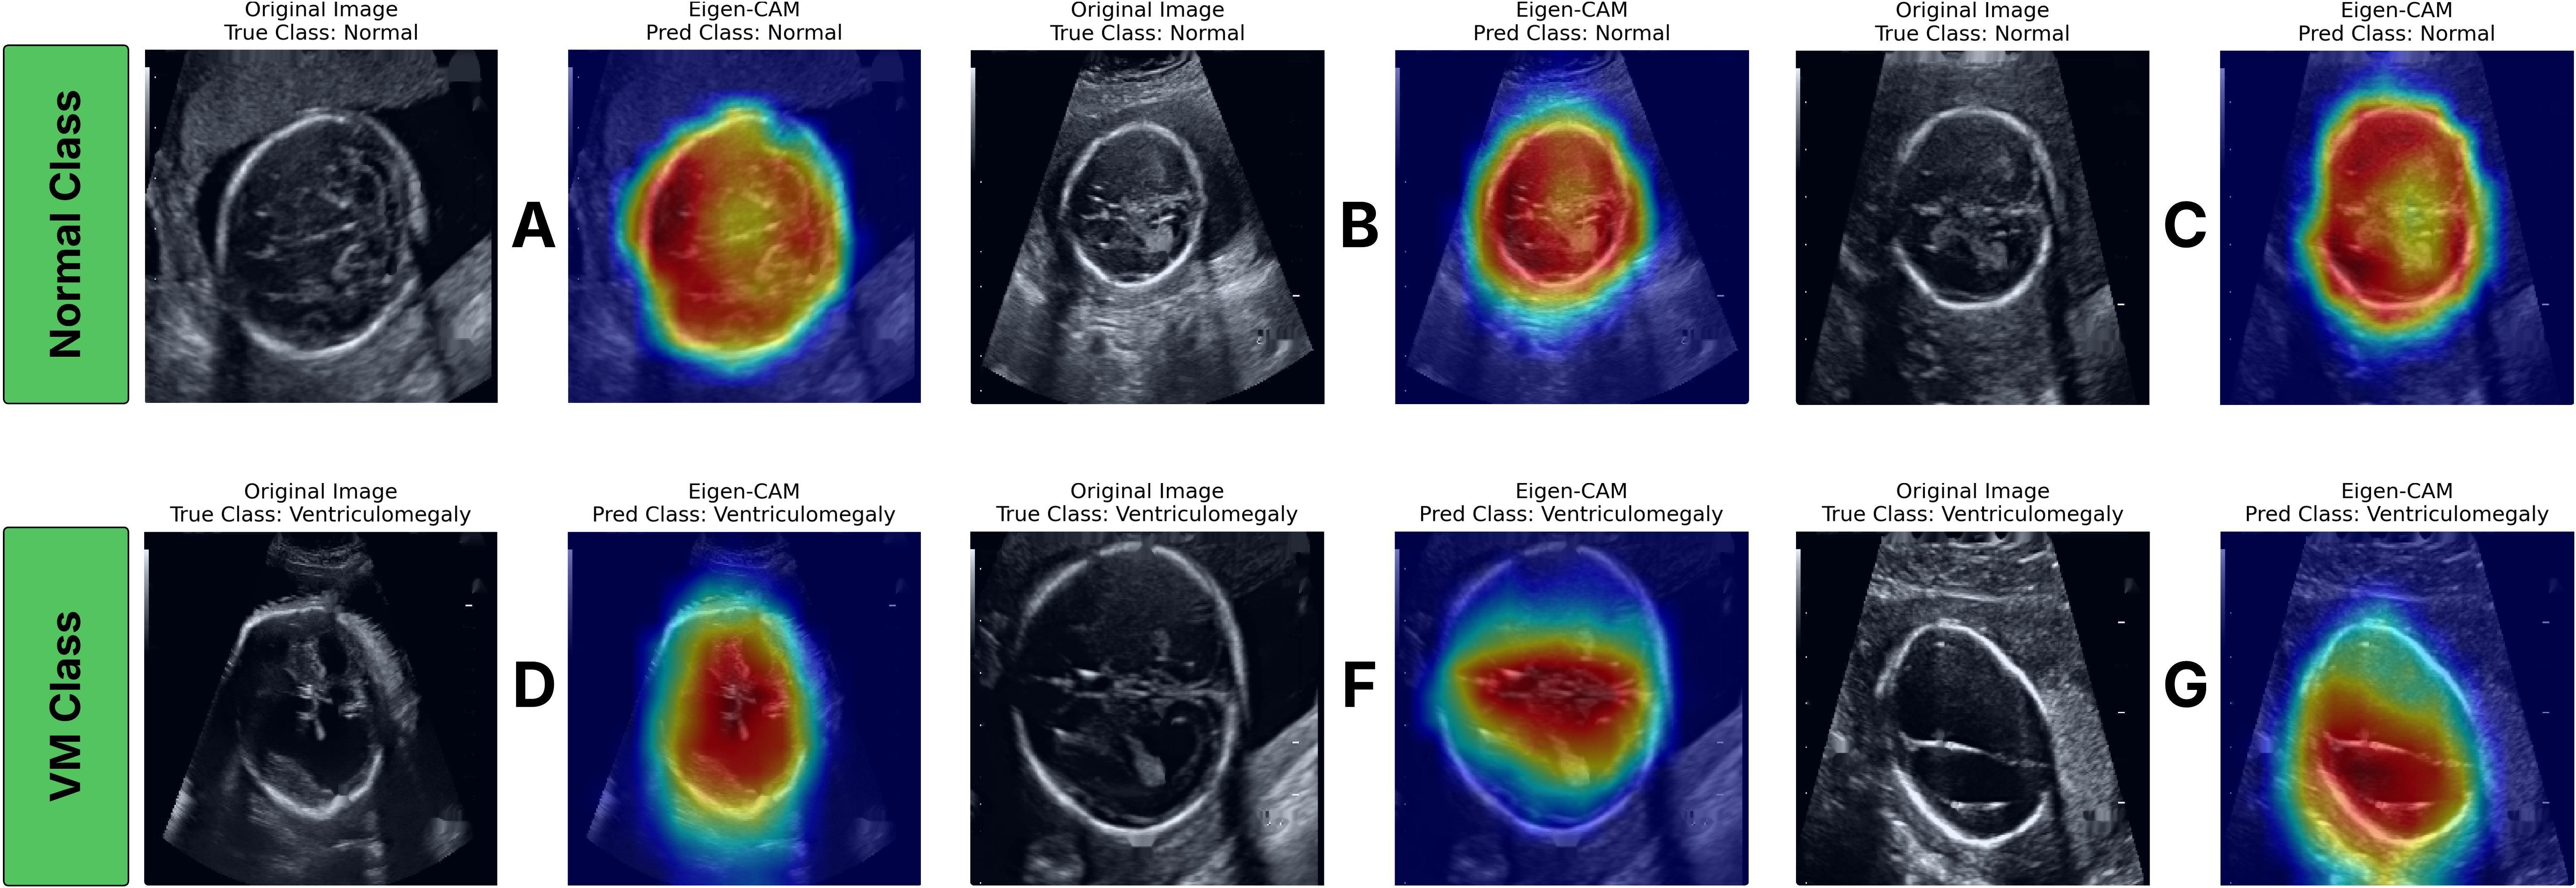

Explainability is a critical component in the clinical translation of DL models, particularly in high-stakes domains such as prenatal imaging. To interpret the decision-making process of the fine-tuned USF-MAE model, we employed the Eigen-CAM method [21], as visualized in Fig. 7. Eigen-CAM provides class activation maps (CAMs) based on the principal components of the model’s activation space, highlighting the regions that most strongly influence its classification decisions without requiring gradient backpropagation.

In the top row of Fig. 7 (A-C), the model correctly focused on the periventricular region and the boundaries of the lateral ventricles for normal cases. In contrast, the bottom row (D-G) demonstrates that, for VM cases, the activation maps concentrated along the dilated ventricular cavities, with high-intensity regions corresponding to the expanded atrial width, the primary sonographic hallmark of VM. The smooth and spatially consistent activation distribution observed across all examples suggests that the model learned to recognize structural features relevant to fetal brain morphology rather than relying on spurious artifacts or background patterns.

While several gradient-based visualization techniques exist, including Grad-CAM and its variants, Eigen-CAM offers distinct advantages when applied to ViT-based architectures such as USF-MAE. Grad-CAM depends on spatial gradients propagated through convolutional feature maps to localize discriminative regions, a mechanism well-suited to CNNs but less effective for transformers, which operate on patch tokens without explicit convolutional kernels. In contrast, Eigen-CAM derives its visualizations directly from the dominant eigenvectors of the attention-based feature activations, capturing the principal modes of variance across all attention heads without gradient computation. This gradient-free formulation preserves the global context inherent to transformer attention mechanisms and avoids the instability or noise amplification that can arise during gradient backpropagation.

Consequently, Eigen-CAM produces smoother, anatomically coherent saliency maps that align closely with the true regions of clinical interest, in this case, the ventricular system. As shown in Fig. 7, the USF-MAE attention heatmaps unambiguously identify the ventricular edges in normal and VM cases. It is clear the model is making its predictions based on physiology-related features. This adds to model transparency and clinical trustworthiness, both of which will be important for eventual regulatory approval and real-world integration into obstetric workflows.

Refer to caption

Figure 7: Representative ultrasound images and corresponding Eigen-CAM [21] heatmap visualizations for correctly classified cases from both classes. Columns show original images and the model’s highlighted regions used for prediction. (A-C) Normal class examples. (D-G) Ventriculomegaly (VM) class examples.